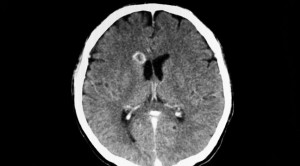

Lesi serebral dengan penyangatan cincin merupakan salah satu temuan tersering pada pindaian otak. Lesi tersebut memiliki beragam diagnosis banding yang merupakan tantangan...(Baca Selengkapnya)